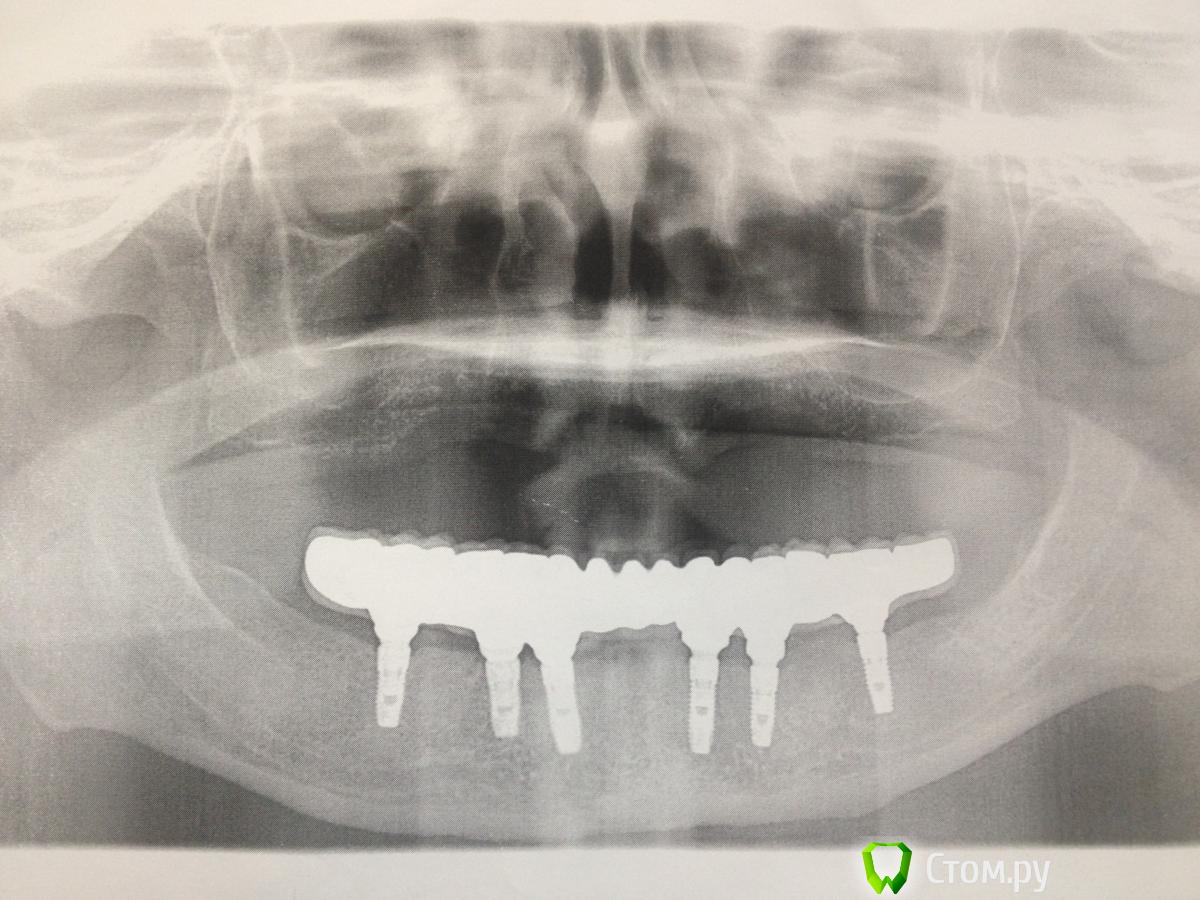

MaxDok Опубликовано 15 февраля, 2014 Поделиться Опубликовано 15 февраля, 2014 (изменено) Интресует правильный ли дизайн промывного пространства ?Критикуйте коллеги. Изменено 15 февраля, 2014 пользователем MaxDok 10 Ссылка на комментарий

MaxDok Опубликовано 15 февраля, 2014 Автор Поделиться Опубликовано 15 февраля, 2014 Красиво! Это цементная фиксация? Каркас литой, а сверху керамика или пластмасса? Спасибо! Цементная,ретракцию везде делал,суперфлоссы во все промежутки в момент цементировки.Каркас изготовлен по технологии лазерного спекания ,облицован керамикой . Ссылка на комментарий

zubovolok Опубликовано 16 февраля, 2014 Поделиться Опубликовано 16 февраля, 2014 Спасибо! Цементная,ретракцию везде делал,суперфлоссы во все промежутки в момент цементировки.Каркас изготовлен по технологии лазерного спекания ,облицован керамикой .какая система имплантов использовалась? Дентиум? Можно по потробней про лазерное спекание? Ссылка на комментарий

MaxDok Опубликовано 17 февраля, 2014 Автор Поделиться Опубликовано 17 февраля, 2014 //// какая система имплантов использовалась? Дентиум? Можно по потробней про лазерное спекание?/// Она самая , что касается технологии изготовлении каркаса ..думаю я не отвечу подробнее чем google )) наберите в поисковике . Ссылка на комментарий